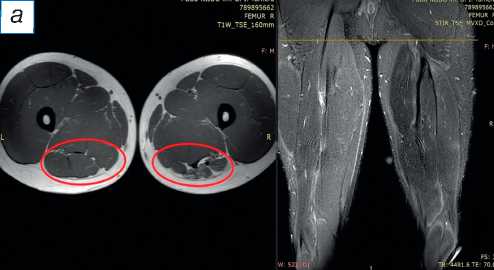

При поступлении в центр пациенту выполнены лучевые методы исследования нижних конечностей, в частности панорамная рентгенография и компьютерная томография (КТ) нижних конечностей; сравнительная МРТ мягких тканей правого и левого бедра (рис. 2). По данным рентгенографии и КТ-исследования, костно-суставной патологии не обнаружено. По результатам МРТ определены повреждения всех трёх мышц различной степени тяжести — SM, ST, BicepsLH (расположены в порядке убывания; см. рис. 2, а ). Длинная головка двуглавой и полусухожильная мышцы, вероятно, были оторваны у места крепления и не подверглись значительной ретракции; начало брюшка полуперепон-чатой мышцы визуализировано на границе верхней и средней трети бедра (ретракция 9 см).

Рис. 2. Сравнительная магнитно-резонансная томография мягких тканей правого и левого бедра (аксиальные и фронтальные срезы): а — изменение нормальной архитектоники полусухожильной, полуперепончатой и длинной головки двуглавой мышцы на уровне верхней трети правого бедра; б — на данном уровне не прослеживается мышечное брюшко полуперепончатой мышцы; в — на границе верхней и средней трети прослеживается мышечное брюшко полуперепончатой мышцы, спаянное с большой приводящей; определяется разница по форме и диаметру поперечника полусухожильной мышцы; г — на уровне средней трети отчётливо проявляются мышечное брюшко полусухожильной мышцы, несоответствие поперечного диаметра полуперепончатой и полусухожильной мышц с контралатеральной стороной, гипертрофия короткой и длинной головки бицепса; д — аналогичная картина и на границе средней и нижней трети. ST ( m. semitendinosus ) — полусухожильная мышца; SM ( m. semimembranosus ) — полуперепончатая мышца; BicepsLH ( m. biceps femoris ) — длинная головка двуглавой мышцы.